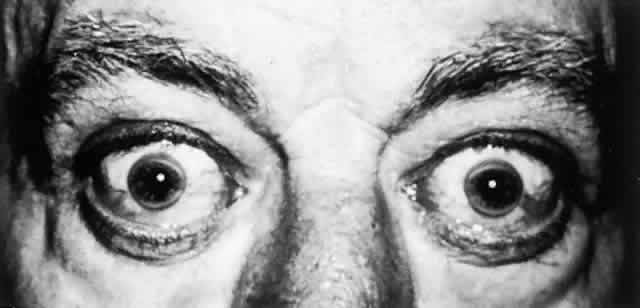

OCULAR FINDINGS. One of the few truly diagnostic and pathognomonic physical signs in clinical medicine is a Kayser-Fleischer corneal pigment ring found in patients with Wilson's disease (Fig. 5).This ring is recognized as a golden-brown, ruby-red, or green band of 1.0 to 3.0 mm, starting at the limbus but at the level of Descemet's membrane.53 The color of the ring is presumably caused by scattering and reflection of incident light and by photointerference effects created by the layers of copper granules. Such variables as size, shape, and unit density of the granules may account for the different appearances of the Kayser-Fleischer ring. The course of the Kayser-Fleischer ring has been well documented.54,55 The site of earliest pigment deposition is an arc in the superior periphery of the cornea from the 10- to 2-o'clock meridian. The arc spreads slowly toward the horizontal plane and gradually broadens. Later in the progression of the ring formation, a band appears inferiorly as a crescent stretching from the 5- to 7-o'clock positions. In time, the two arcs meet. With treatment, the sequence of events is reversed, and after the copper has reabsorbed, a pitted or beaten silver pattern may become apparent at the previous site of the ring. This is an indication that treatment has produced a negative copper balance.49 Decreased visual acuity is not a problem. Rarely, copper is deposited in the crystalline lens, giving an anterior subcapsular “sunflower” cataract.